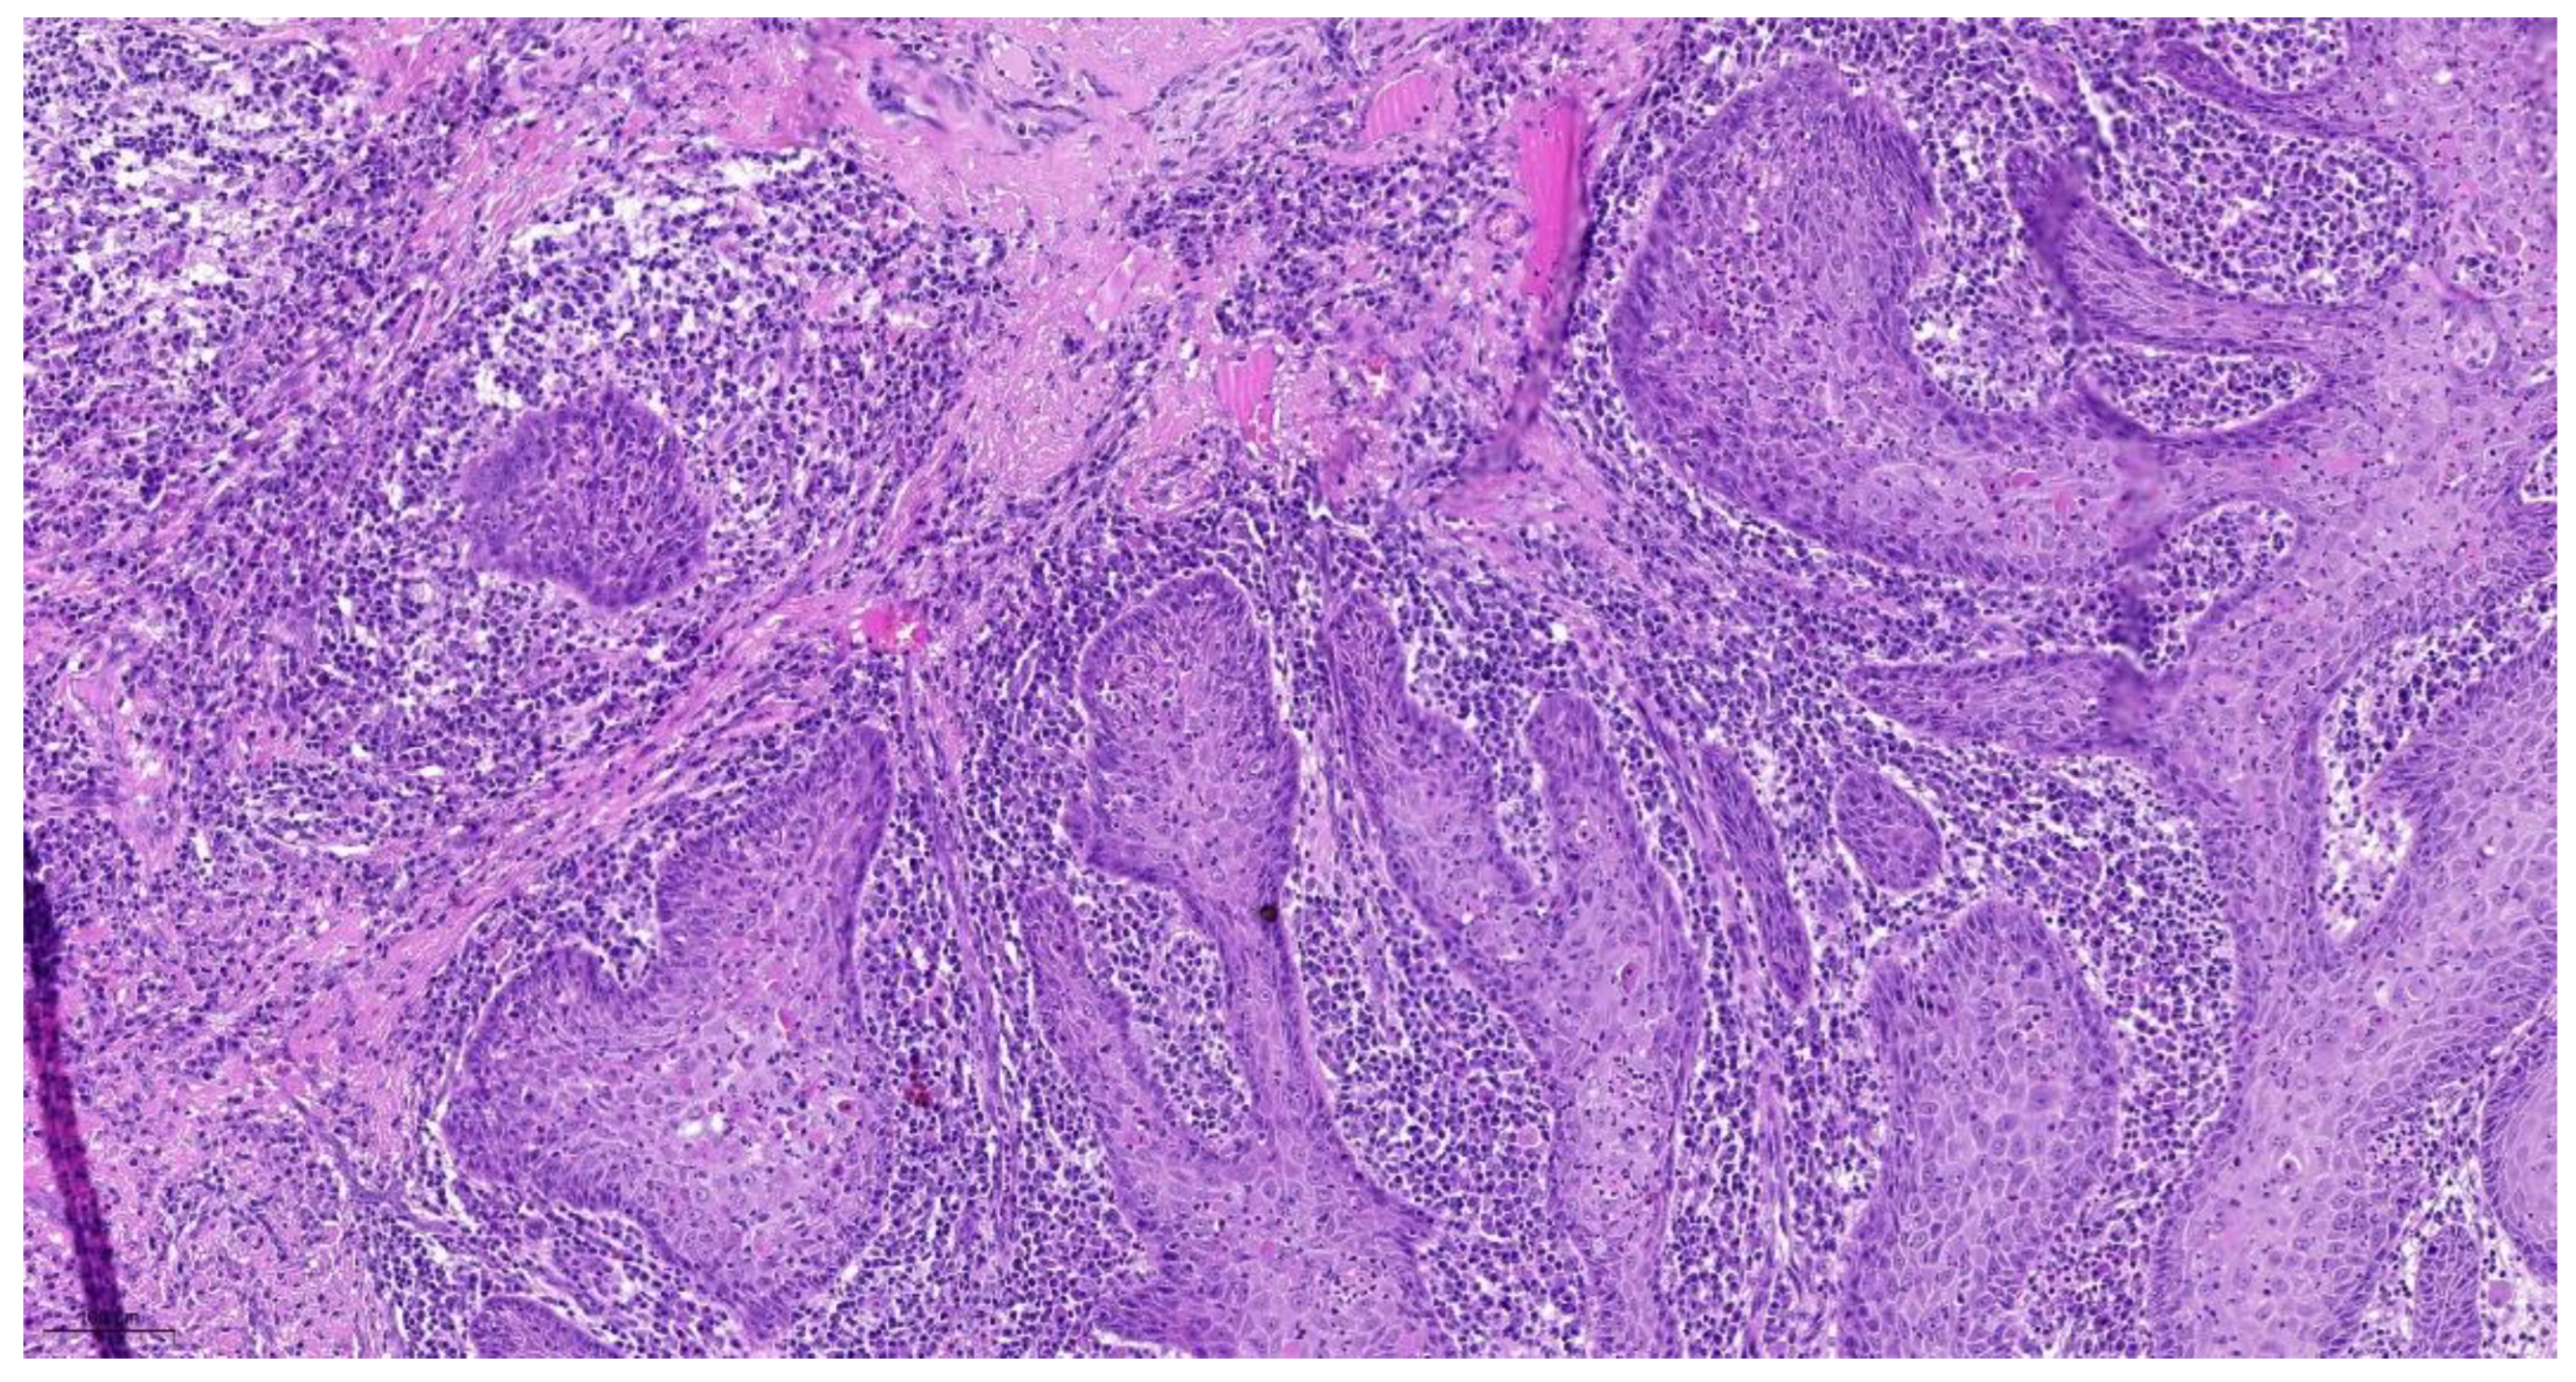

| Tumor Budding * (TB) | No tumor budding | Score 1 |

| 1–5 tumor buds/HPF | Score 2 | |

| >5 tumor buds/HPF | Score 3 | |

| Cell Nest Size (CNS) | >15 cells per nest 5–15 cells per nest 2–4 cells per nest | Score 1 Score 2 Score 3 |

| single cell invasion | Score 4 | |

| Cellular Dissociation Grade (CDG) | Sum TB + CNS = 2–3 Sum TB + CNS = 4–5 | CDG-1 CDG-2 |

| Sum TB + CNS = 6–7 | CDG-3 |